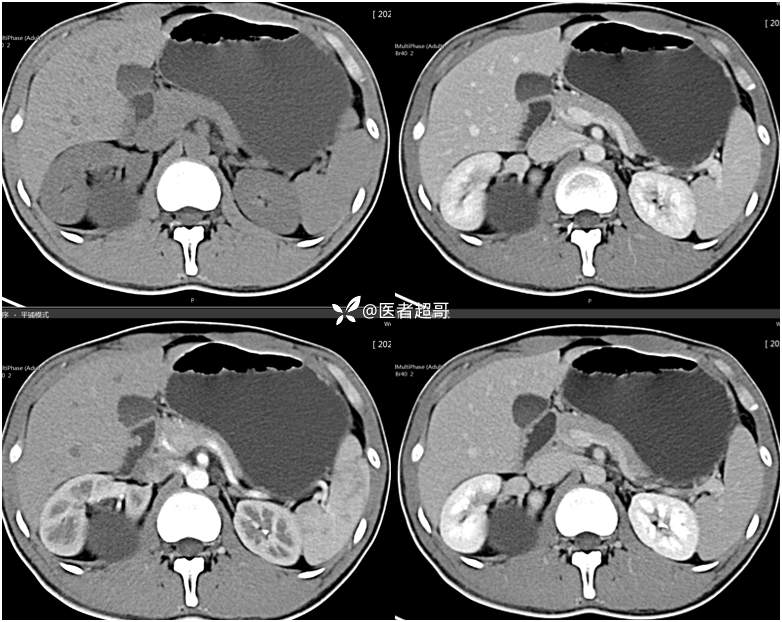

【影诊笔记754】腰痛就诊,腹膜后实性占位,请诊断分析!

主 诉:腰痛2月。

现病史:患者2月前无明显诱因出现腰背部疼痛,夜间为著。患者无头痛、头晕,无恶心、呕吐,无胸闷、憋气,无腹痛、腹胀。无尿频、尿急、尿痛等现象。患者在院外未作特殊治疗。为求进一步诊疗,来我院肾内科门诊就诊。门诊行双肾、输尿管、膀胱(前列腺)彩超提示:腹膜后实性占位。患者遂来我科就诊。我科以“腰痛”收治入院,患者自发病以来,神志清,精神可,饮食可,睡眠差。小便如上述,大便未见明显异常。体重无明显增减。